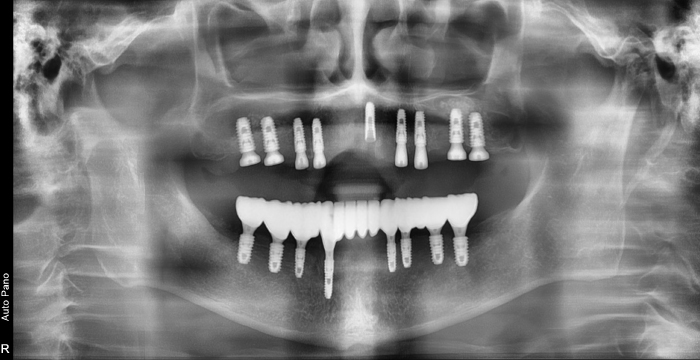

무치악 임플란트도 즉시 식립 임플란트로!

치아가 모두 상실된 경우 그냥 방치하게 된다면 잇몸뼈(치조골)가 계속 소실됩니다. 서울바른훈치과의 무치악임플란트는 다년간의 임상경험이 풍부한 서울대출신의 의료진이 직접 시술은 물론 자체 디지털 기공실 협진 시스템을 갖추고 있습니다.

즉시 식립 임플란트 전후 사례

• 식립 전

식립 후